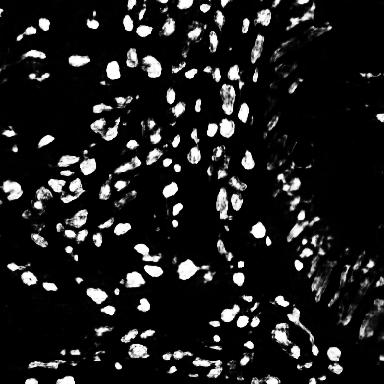

In this work, I propose a supervised deep learning-based model for accurate automatic cell nuclei segmentation. Given a tissue image, it begins with a deep convolutional neural network model to generate a probability map. Next, a threshold and morphological operations are applied to distinguish the background and the cells.

One of the significant benefits of the proposed method is that it can be applicable to different staining histopathology images taken of different patients. Due to the feature learning characteristic of deep convolutional neural network and the high level shape prior modeling, the proposed method is general enough to work properly across different image scenario like healthy, adenoma, hyperplasia.

Finally, I validated the proposed algorithm on several histopathology images using a range of different tissue from various patients with differents diseases.